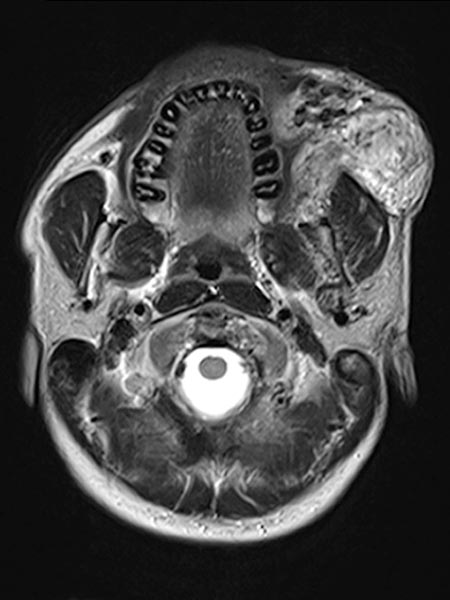

Axial, T2-weighted MRI at the level of the cheek shows the AVM to be relatively hyperintense with edema of the surrounding tissue and extension to the left mandible. In the rostral section some black flow voids are visible as a sign of arteries with fast flow within the AVM.

Coronal fat-suppressed T1-weighted MRI after contrast administration shows the inhomogeneous marked enhancement of the AVM. This is typical of an AVM in the stage of proliferation (corresponding to rapid enlargement) and correlates well with the edema in the T2-weighted images.

Coronal T2-weighted fat-saturated MRI showing hyperintense edema within the AVM and flow voids due to fast-flow arteries.

Inhomogeneous, peripheral enhancement of the proliferating AVM in this axial fat-suppressed T1-weighted MRI after contrast administration. No circumscribed component that is actually solid, unlike in a true vascular tumor.